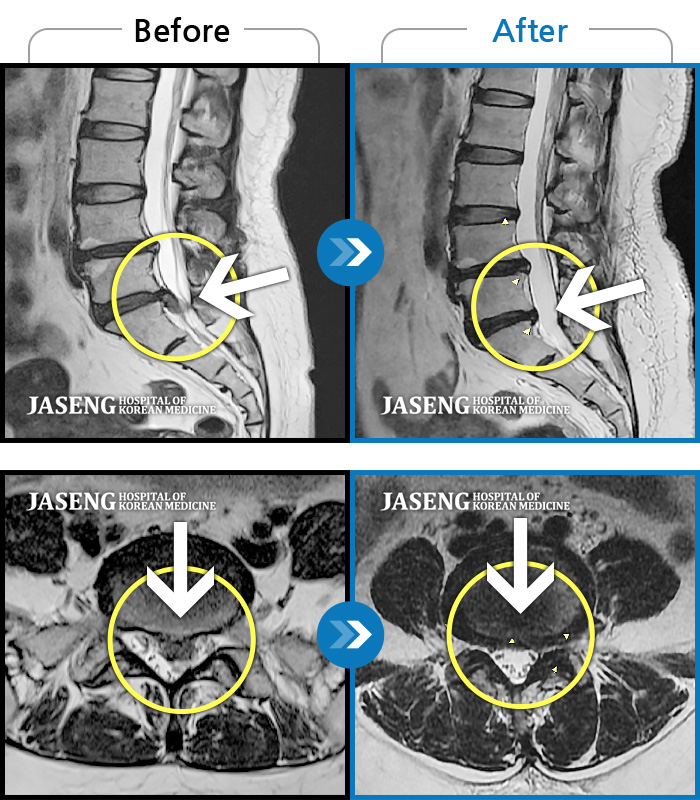

허리디스크

해운대 · 김상돈 원장

아래쪽 허리와 우측 골반에 통증이 있었습니다.

촬영시기

2019.08.26 ~ 2025.08.09

2025.08.14